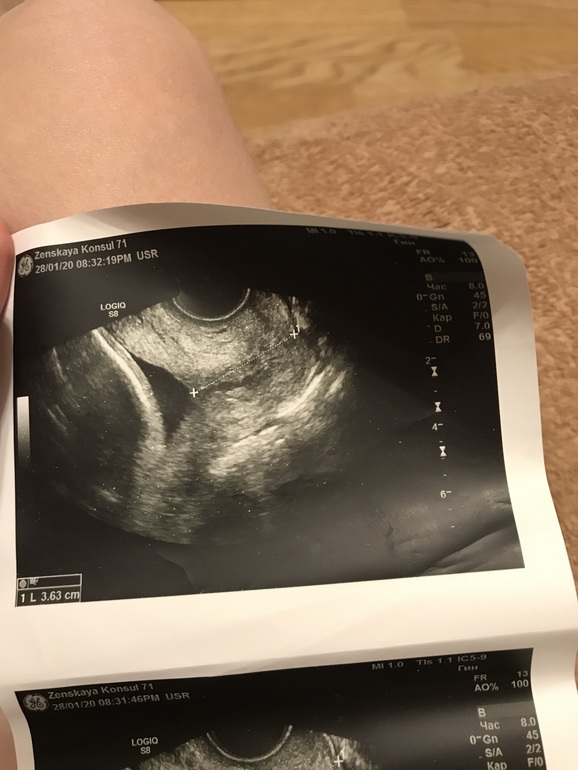

Цирвикометрия, как такое возможно вообще. Фото прилагаю

Вопросы про УЗИ, обследования и анализы: что, где, как, когда?Я с 20 недель уже замучилась мониторить шейку. Уже глаз дёргается. Вчера делала узи в ЖК, блин и своими глазами видела как воронка то появляется, то исчезает. При том без воронки шея 4.4! У меня даже в 12 недель такой шеи не было. Стоило повернуть датчик, как появляется внушительных размеров воронка и шея 3,3-3,6. Как такое возможно? Что мне делать вообще? Бежать сдаваться в рд (только 2 недели назад выписали с миром с шеей 30 мм и закрытыми зевами). И вот такая ситуация с подросшей шейкой, но воронкообразным Зевом. Гинеколог назначила узи через 7 дней, а мне пипец страшно!!! Записалась на пятницу, не выдержу неделю. Что это за фокусы с УЗИ. Разница между фото меньше минуты. Потом она ещё посмотрена сверху по животу, воронки по животу не видно. Поэтому она меня и отпустила. А я весь мозг себе уже вынесла, начиталась. Может было у кого подобное? Я предполагаю, что на фоне тонуса периодического шея к 20 неделям сократилась с 41 мм до 30 мм. Сейчас матка спокойная, длина шейки вернулась, но та часть которая уползла ранее уже не такая эластичная и образует воронку.